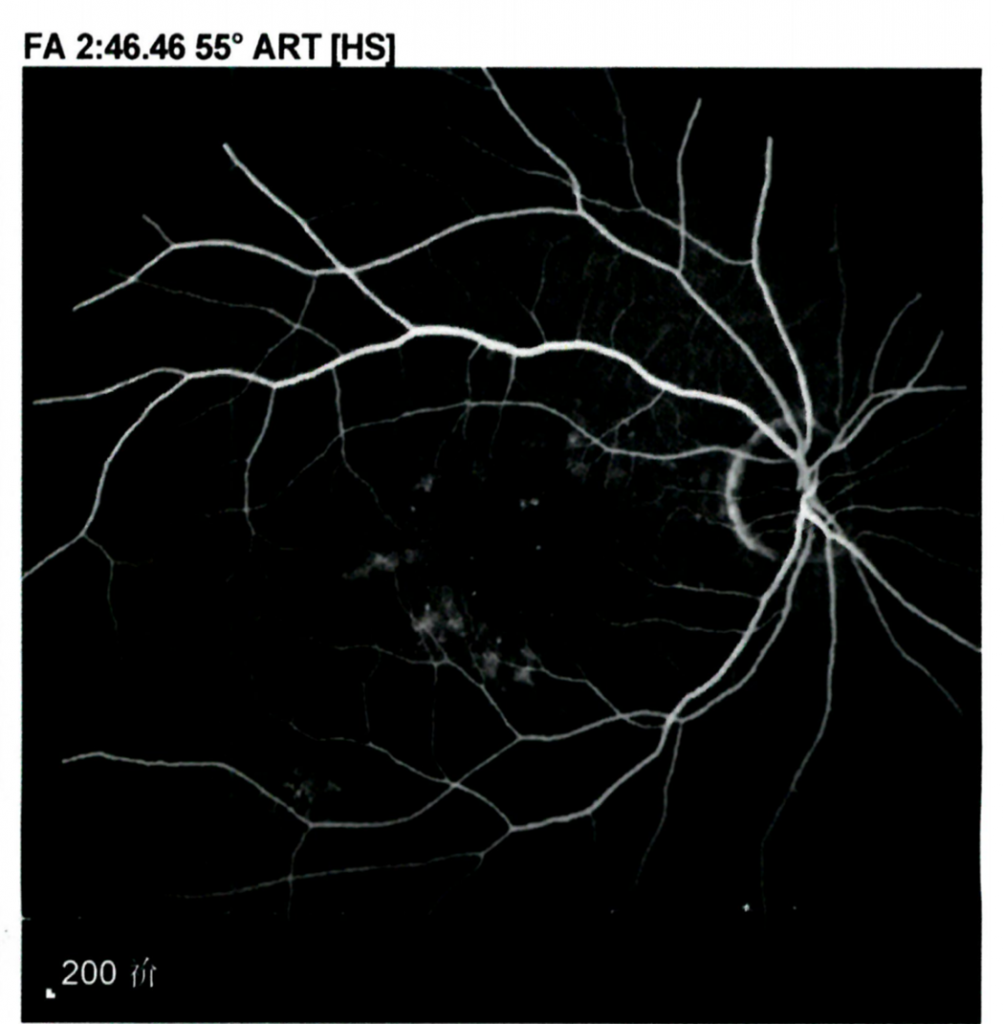

眼底造影显示,经JWK001给药治疗后

患者眼睛磨砂状阴影大范围减少,如下图:

治疗后